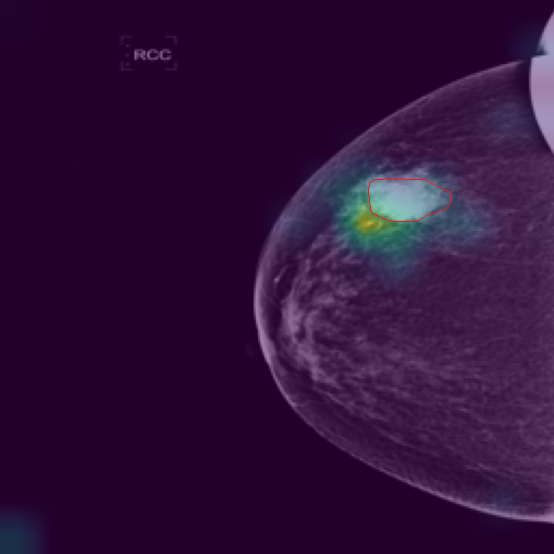

5.9 ViKL Provides Evidence for Clinical Decision

In our earlier sections, we discussed how ViKL enhances the image branch’s capability for detailed feature extraction by using text and manifestations that describe localized lumps. To directly observe this enhanced feature extraction ability, we utilize the class activation map (CAM) [62], a common tool for visualizing neural network activations. Specifically, we employ Grad-CAM [63] to generate activation maps from the third layer of the ResNet50 model, which has been fine-tuned using ViKL on the MKVL dataset. Additionally, for accurate visualization and comparison, we include markings of lumps as annotated by professional radiologists. The results of this visualization are showcased in Fig. 6. These visualizations demonstrate ViKL’s effective localization of small lesions, highlighting its refined ability to capture minute features in medical imaging.